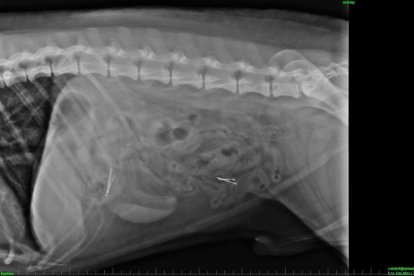

Els veterinaris van procedir a realitzar les proves pertinents. D'aquesta manera, les radiografies van confirmar que el gos tenia al seu interior agulles com les d'altres casos que s'han fet públics a la zona. Els veterinaris van optar per operar l'animal «per prevenir possibles problemes», tot i que expliquen que en alguns casos aquests objectes poden ser expulsats amb els excrements amb dietes amb molta fibra, però les analítiques van confirmar un «augment de glòbuls blancs, fet que podia indicar una possible infecció».